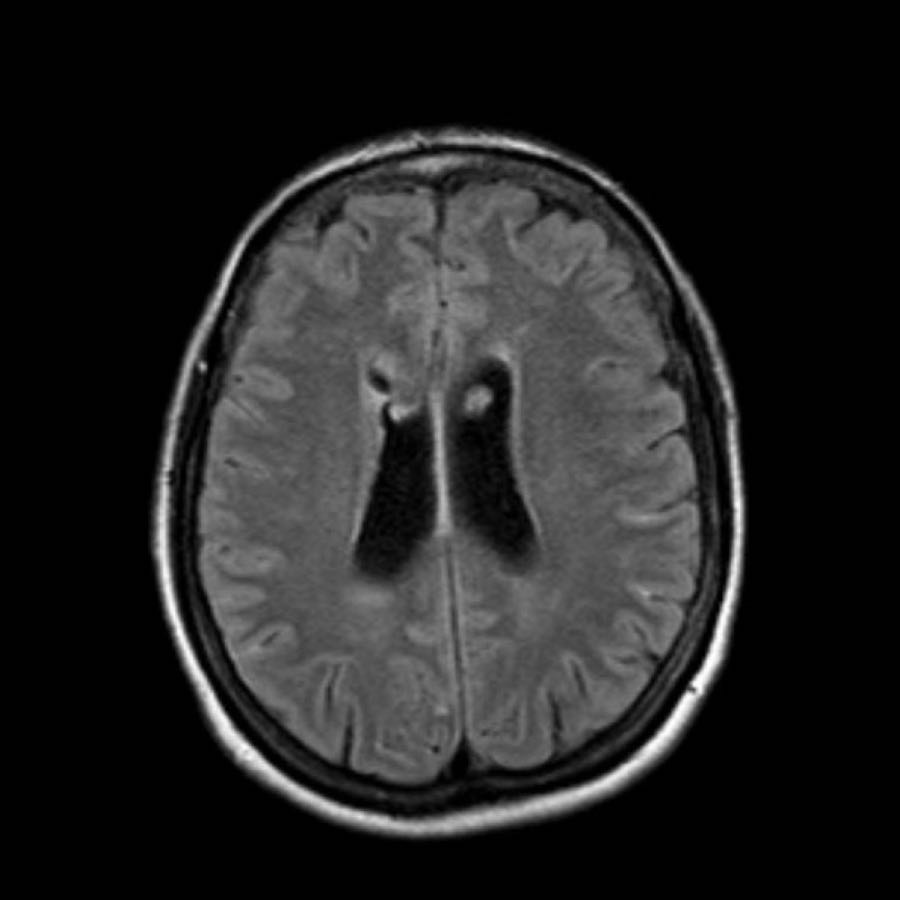

Bệnh nhân này nhập viện với não úng thủy do xuất huyết não thất (hình bên trái).

Lưu ý vùng tăng tỷ trọng rất nhỏ tại đồi thị trái, là điểm khởi phát của xuất huyết.

Theo dõi một ngày sau (hình bên phải).

Bệnh nhân được phẫu thuật đặt dẫn lưu não thất để điều trị não úng thủy.

Lưu ý đồi thị bên trái giảm tỷ trọng với ổ tăng tỷ trọng dai dẳng ở vị trí trong.